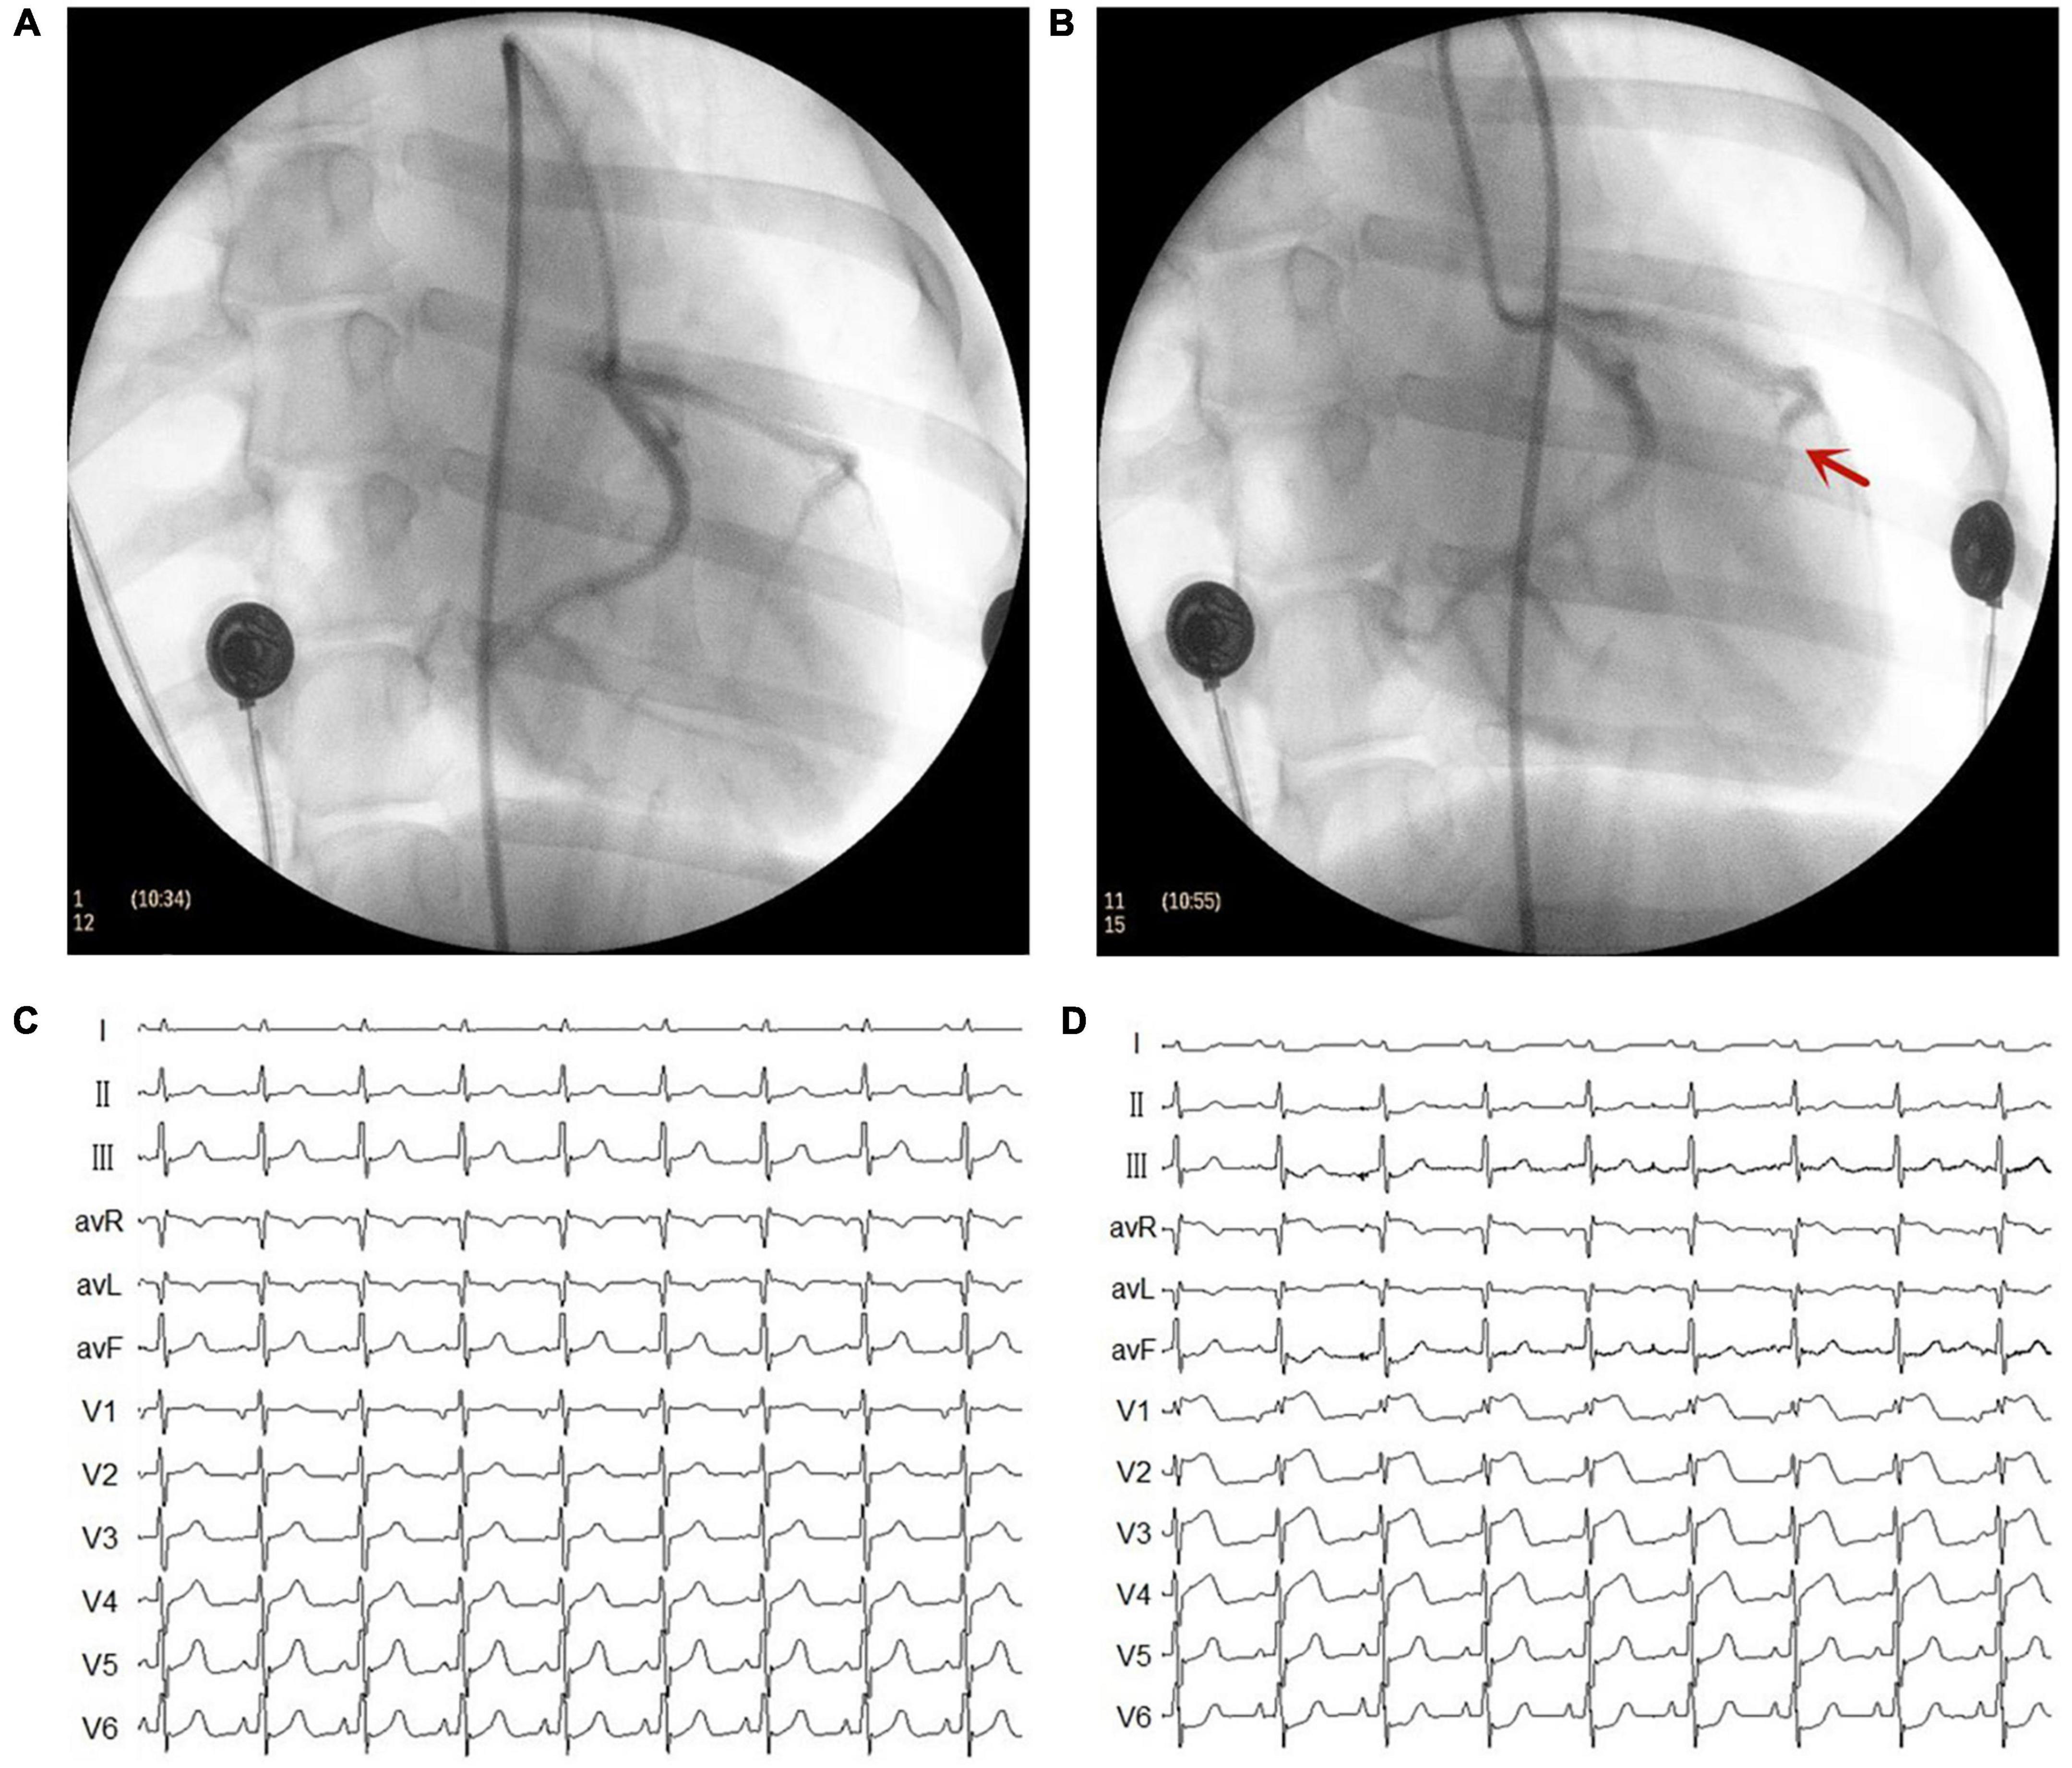

The MI model was established using catheter intervention. After administering stable anesthesia to all dogs, we injected 1000 U of heparin; then, we inserted hemostatic sheaths into their right femoral artery. Using X-ray fluoroscopy, a 5 F catheter was inserted into the left coronary artery to determine a coronary angiogram. Keeping the 5 F catheter positioned at the left anterior descending artery, a Radifocus SP catheter was delivered to the distal anterior descending artery through the 5 F catheter. A gelatin sponge with normal saline was injected into the distal anterior descending artery in 15 dogs. Notably, if the ST segment had no significant changes, the gelatin sponge with normal saline was reinjected. When the chest lead ST-segment was elevated, acute MI was achieved (Figure 1). The control group consisted of the other seven dogs injected with normal saline at the distal end of the anterior descending branch. Later, the animals were allowed to recover for 4 weeks. Figure 2 shows the time axis of procedures used in this study.

Figure 1. Representative images of X-ray and electrocardiogram (ECG) changes during the myocardial infarction (MI) model. (A) Left coronary artery arteriography before gelatin sponge injection. (B) Left coronary artery arteriography after gelatin sponge injection. Notably, the distal anterior descending artery had obvious stenosis. (C) ECG before gelatin sponge injection. (D) ECG after gelatin sponge injection, the chest lead ST segment was elevated.